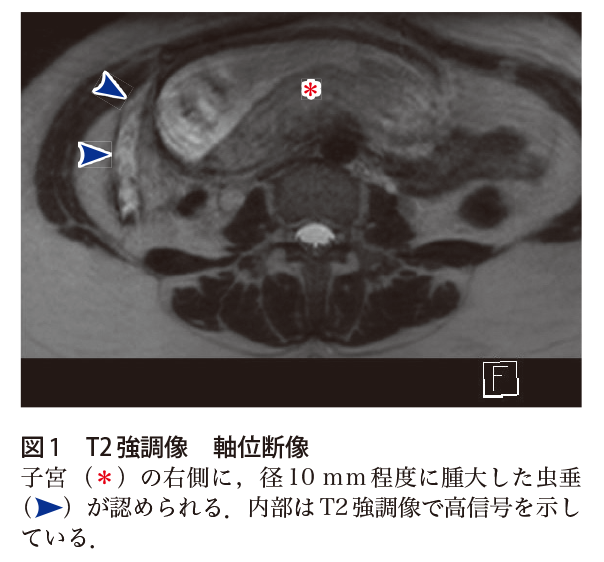

画像診断cafe 虫垂炎-虫垂炎17例中16例(941%)に手術が施行され, 病理組織学的診断は,壊疽性虫垂炎11例,蜂窩織炎 性虫垂炎3例,慢性虫垂炎2例であった(表2)。壊 疽性虫垂炎では,横径6mm以上の虫垂腫大が909%, 虫垂壁の全周性の同定が1%,虫垂壁の部分的欠損虫垂炎においては,画像診断の役割は非常に大きい. 加えて,虫垂炎の診断が得られた場合,さらに虫垂 の炎症の進行を画像的に評価することで,その治療 方針に大きく寄与することとなる. 当施設ではerで小児科医のトリアージ・初期評

虫垂炎とct画像診断のポイントについて動画でまとめました。 以下についてまとめました。 ・虫垂炎とは?場所は? ・虫垂炎の原因は? ・虫垂炎のct画像診断のポイントとは? 1,虫垂自体の炎症所見 2,周囲への炎症波及所見 3,穿孔所見 参考になれば嬉しいです。虫垂の解剖の理解に重点をおいた虫垂炎画像診断のためのスライドです. 初期研修医や医学生,自信を持って虫垂炎を除外・診断したい若手医師のために作成しました.まずは虫垂炎の診断に自信をつけましょう. *** 以前のスライドに大幅追記・修正したものになります.画像検査の読み方 虫垂炎 画像読影の基本 急性虫垂炎の画像診断は,超音波検査や ct検査が選択されることが多い。超音波検 査は肥満患者や腸管ガスが貯留している患者 では診断が困難となり,ct検査では内臓脂 肪が少ない患者やイレウスを合併した患者で